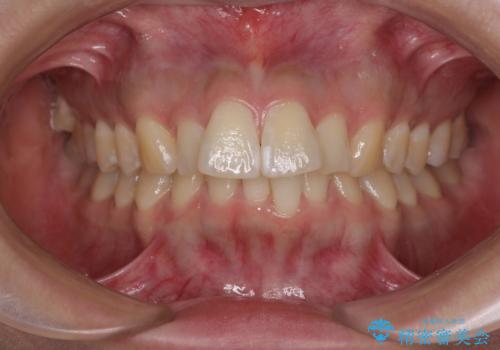

- デコボコと飛び出した前歯を治したいとのことで来院された患者様です。

ゴムかけを活用して上顎歯列全体を後方移動し、IPR(歯と歯の間を削る)によってデコボコが解消するように設計し、インビザラインにより治療を行うこととしました。

後方移動に際し、上下顎の親知らずは4本とも抜歯することとしました。